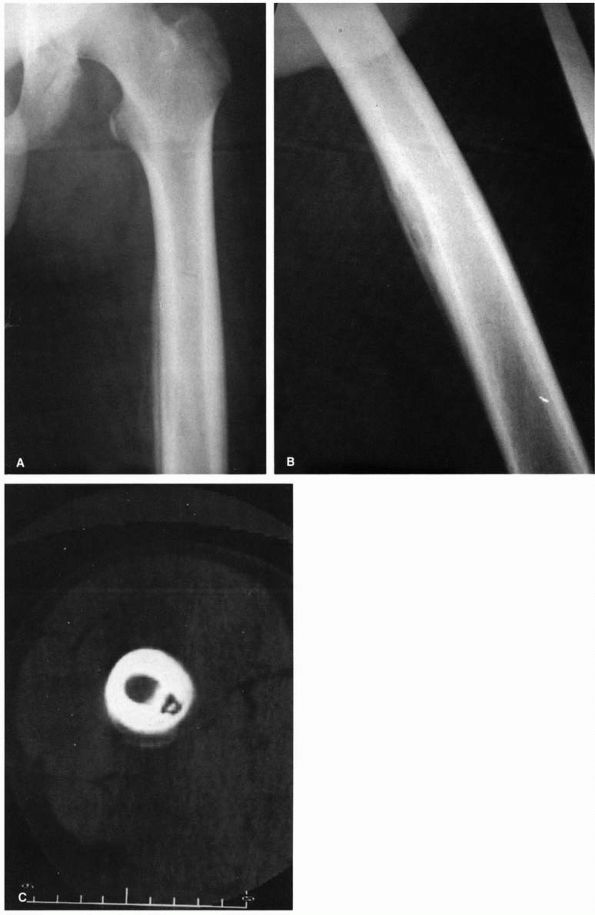

FIGURE 5-2. Radiographs of a child with progressive radiographic changes as the result of acute hematogenous osteomyelitis of the tibia. (A) AP radiographs of the tibia that demonstrate soft tissue swelling with loss of the normal tissue planes. (B)

Radiographs of the same leg taken 2 weeks after the one in A. Note the early mottled appearance of the tibia with a small amount of periosteal new bone seen on the medial cortex of the tibia. (C) Five weeks after presentation this AP radiograph of the tibia shows progressive destruction of the entire diaphysis and proximal metaphysis of the tibia. (Courtesy of Dr. R.H. Hensinger) |